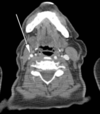

2

Q

A

left horizontal semi circular canal